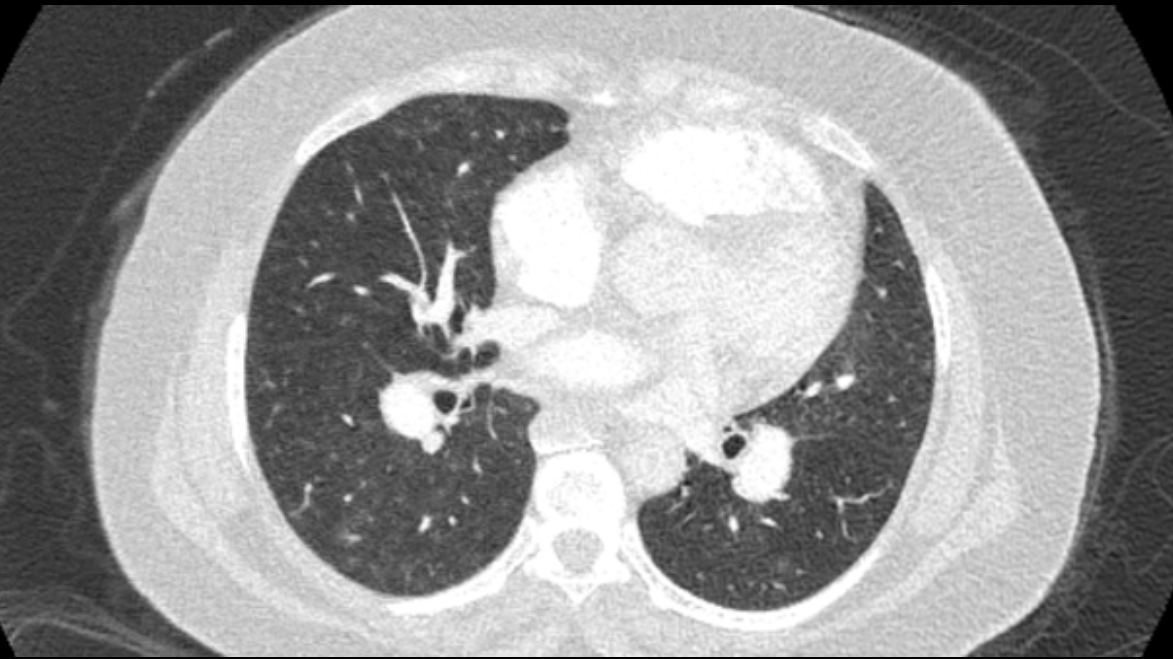

Clinical Case [Uncaptioned image] [Uncaptioned image]

Image Findings: The patient underwent contrast-enhanced computed tomography which showed features of a congested liver with flip-flop pattern of enhancement. Hepatic veins show hypoattenuation on delayed phase. An accessory hepatic vein is also noted in segment VI. A diagnosis of Budd Chiari syndrome (BCS) was made on the basis of the clinical and imaging features. The patient was referred to the interventional radiology team for an endovascular rescue. On conventional venogram, the diagnosis of BCS was confirmed as the hepatic veins were thrombosed. An accessory segment VI hepatic vein was noted draining into the IVC…